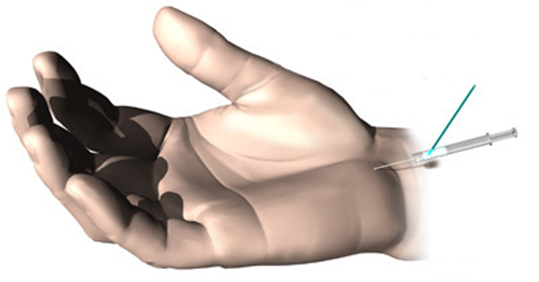

비수술적 치료법

손 저림이 있다고 해서 반드시 수술을 하는 것은 아닙니다.

가끔씩 손 저림이 나타나는 초기의 경우 일상생활에서 손목이 굽혀지는 자세를 피해 주기만 해도 증상이 좋아지고, 약물 복용없이 손목을 퍼주는 부목만으로도 치료가 됩니다.

손 저림이 지속적으로 나타나는 경우에는, 손목을 퍼주는 부목과 함께 소염진통제의 약물 복용이 필요하고, 손목 내에 약물을 주시하는 것이 좋은 치료방법입니다.

그러나 이 치료방법은 2~3주에 걸쳐 세번 정도까지만 시도해 볼 수 있습니다.

가끔씩 손 저림이 나타나는 초기의 경우 일상생활에서 손목이 굽혀지는 자세를 피해 주기만 해도 증상이 좋아지고, 약물 복용없이 손목을 퍼주는 부목만으로도 치료가 됩니다.

손 저림이 지속적으로 나타나는 경우에는, 손목을 퍼주는 부목과 함께 소염진통제의 약물 복용이 필요하고, 손목 내에 약물을 주시하는 것이 좋은 치료방법입니다.

그러나 이 치료방법은 2~3주에 걸쳐 세번 정도까지만 시도해 볼 수 있습니다.